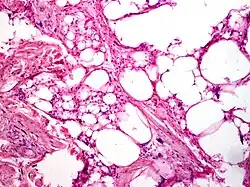

Histologically, bland spindle mesenchymal cells and mature fat make up the majority of the tissue in pleomorphic lipoma. Furthermore, multinucleated large cells with radically positioned nuclei in a "floret-like" pattern are strewn among the spindle cells. The histological spectrum is rather diverse, ranging from a tumor that primarily consists of spindle cells with only a few fat cells to a tumor that resembles an average lipoma with few spindle cells. Cytologically, multinucleated large cells feature irregular, hyperchromatic, and considerably unusual nuclei, while spindle cells have single elongated hyperchromatic nuclei and inconspicuous nucleoli. The two cell types' mitoses are uncommon. Collagen bands that resemble ropes are sporadically spaced throughout the cellular components and are typically a crucial diagnostic indicator for pelomorphic lipoma.[10]